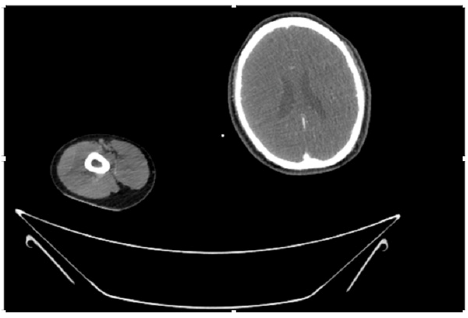

55-years-old chronic smoker had acute, severe pain in the right upper limb for one week; it was cold upto mid arm with skin discoloration. He also noticed numbness and weakness of movement of elbow joint. He underwent below elbow amputation in February 2023 for acute ischemia of left upper limb. He was a current chronic smoker; 15 pack year. General condition was weak; temperature was normal; blood pressure was 100/60mmHg; heart rate was 92/minutes with sinus rhythm; SpO2 was 97% on air; heart was normal. In lower extremities, all peripheral pulses were intact. Local Examination of right upper limb revealed as follows: tenderness; coldness; discoloration; decreased motor function and sensory modalities. Axillary, brachial and radial pulses were not palpable. Hand-held Doppler failed to detect any signal in arterial system; therefore, we arranged for emergency embolectomy. complete occlusion of right upper limb arterial system Full blood count showed high hemoglobin (14.6gm%); normal total WBC and platelet count. Coagulation profile was normal. Parenteral unfractionated heparin, antibiotics, tramadol, proton-pump inhibitors, anti-platelets and HMG CoA reductase inhibitors were given. Doppler ultrasound demonstrated complete occlusion of right upper limb arterial system. CT Angiogram illustrated occlusion of subclavian artery downwards on both sides. Figures 1-14 shows complete occlusion of right subclavian artery without collaterals. On Day ‘2’ of admission, the patient passed black tarry stool for 3 times. However, the vital signs were stable; blood pressure was 100/60mmHg; heart rate was 92/min; SpO2 was 97% on air; the abdomen was soft and not tender. Above elbow amputation was done on Day ‘2’ of admission. Intra-operative findings were as follows: (1) no active bleeding at brachial artery; (2) thrombosis along brachial artery; (3) muscle color and consistency were not healthy.

Figure 4: CT Angiogram at neck showing normal brachio-cephalic trunk, common carotid artery, and narrow right subclavian artery.

Figure 5: CT Angiogram at neck showing normal brachio-cephalic trunk, common carotid artery, and narrow right subclavian artery.

Figure 6: CT Angiogram at neck showing brachio-cephalic trunk, common carotid artery and narrow right subclavian artery.

Figure 7: CT Angiogram at neck showing brachio-cephalic trunk, common carotid artery and narrow right subclavian artery.

Figure 10: CT Angiogram at upper arm showing totally occluded right axillary artery; normal internal carotid artery and external carotid artery.